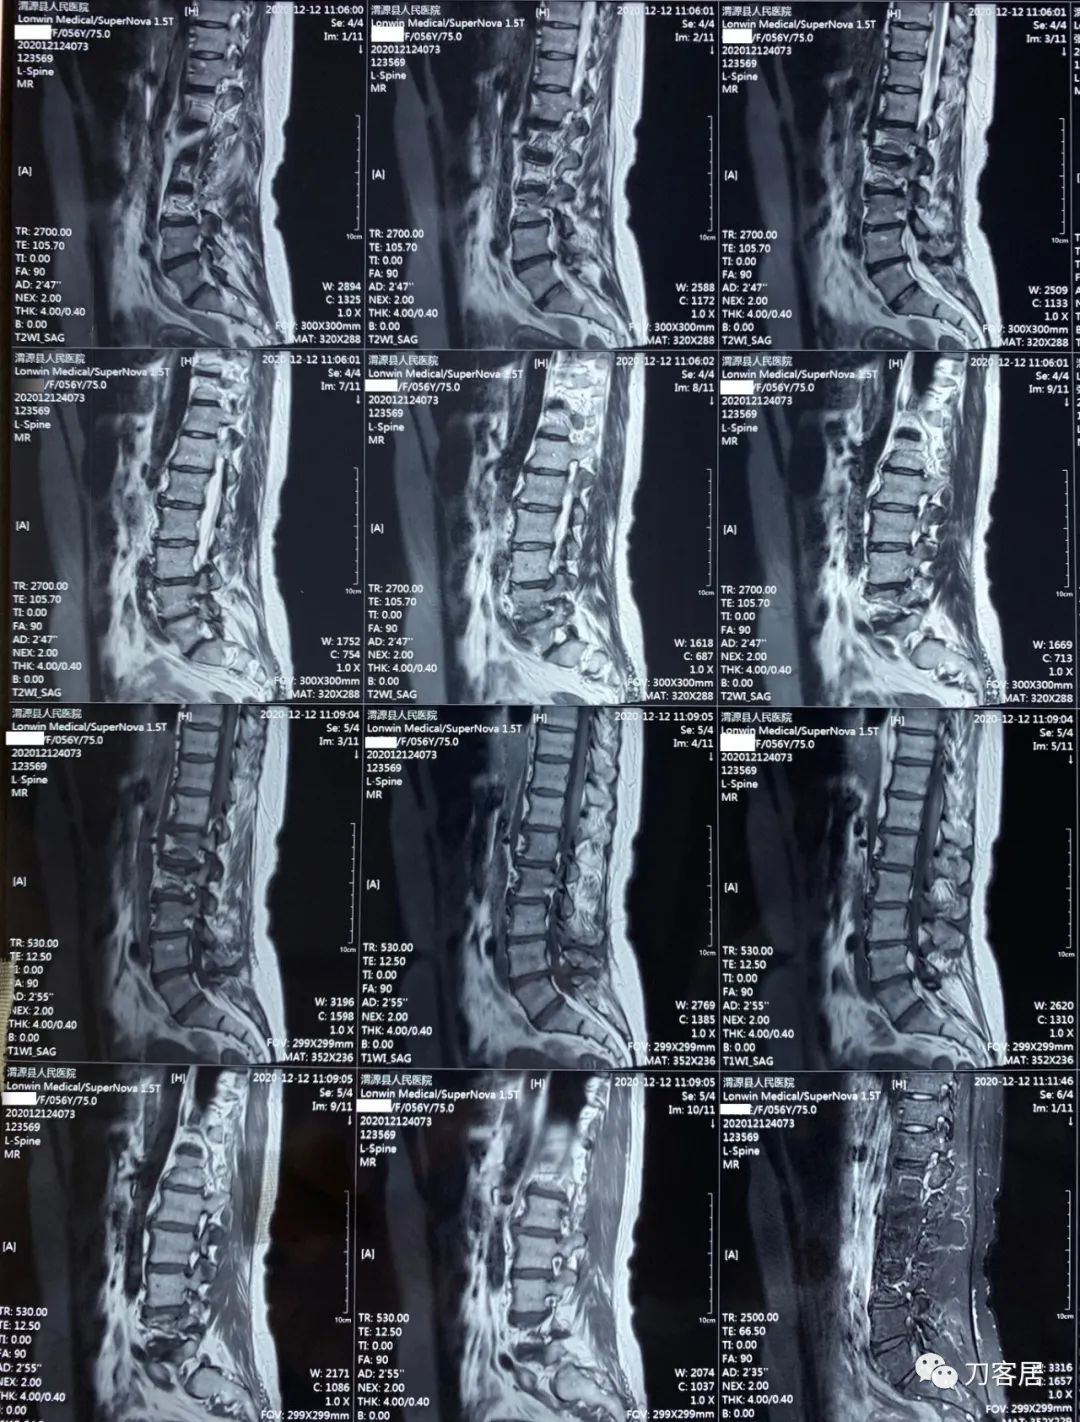

2021年12月12日去渭源县医院做颈椎腰椎MRI,提示1.腰椎侧弯畸形并骨质增生,2. L5S1椎体终板炎(I型), 3. L1-S1椎间盘变性并腰2-4,腰5骶1椎间盘膨出,腰4-5椎间盘突出并相应平面继发性椎管狭窄。2020年12月中旬于渭源县医院行骶管注射2次6针后睡眠改善,

从这个患者的影像资料分析,颈椎间盘突出问题不大,没有明确的上位神经元损伤表现,所以,不考虑颈椎和胸椎问题。腰椎侧弯畸形,但不严重。因为存在腰椎侧弯,使得腰椎MRI在扫描切面的时候,显示的椎间盘突出或椎管狭窄会有一定的误差,所以,又加做了经椎间盘的CT平扫,影像表现并不严重,综上,腰椎间盘突出,腰椎管狭窄,腰椎侧弯,不考虑手术治疗。同时,患者的主要痛苦是心理疾病,而不是器质性疾病,所以,以心身疾病治疗为主。虽然患者骨密度检查结果提示正常,但X线片显示骨质疏松,且其症状也与骨质疏松的症状有符合之处,比如静息痛,不能入睡,动作及姿势变换时痛加重等,所以,给予实验性抗骨质疏松治疗,以观疗效。

3. 2020年12月11日,在甘肃省中医院脊柱骨二科看病,吃中药,治疗半月,中途12月12日去渭源县医院做了核磁检查,提示腰椎侧弯畸形并骨质增生,腰5骶1椎体终板炎(I型), 腰1-骶1椎间盘变性并腰2-3,腰3-4,腰5骶1椎间盘膨出,腰4-5椎间盘突出并相应平面继发性椎管狭窄。